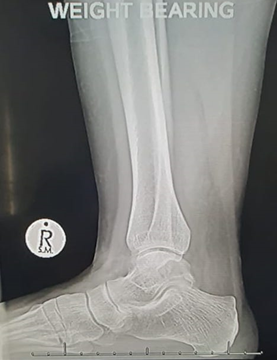

- X-rays – normal bony anatomy; soft tissue swelling may be evident.

- Stress views are useful in diagnosing ligament injuries (compare to the contralateral side).